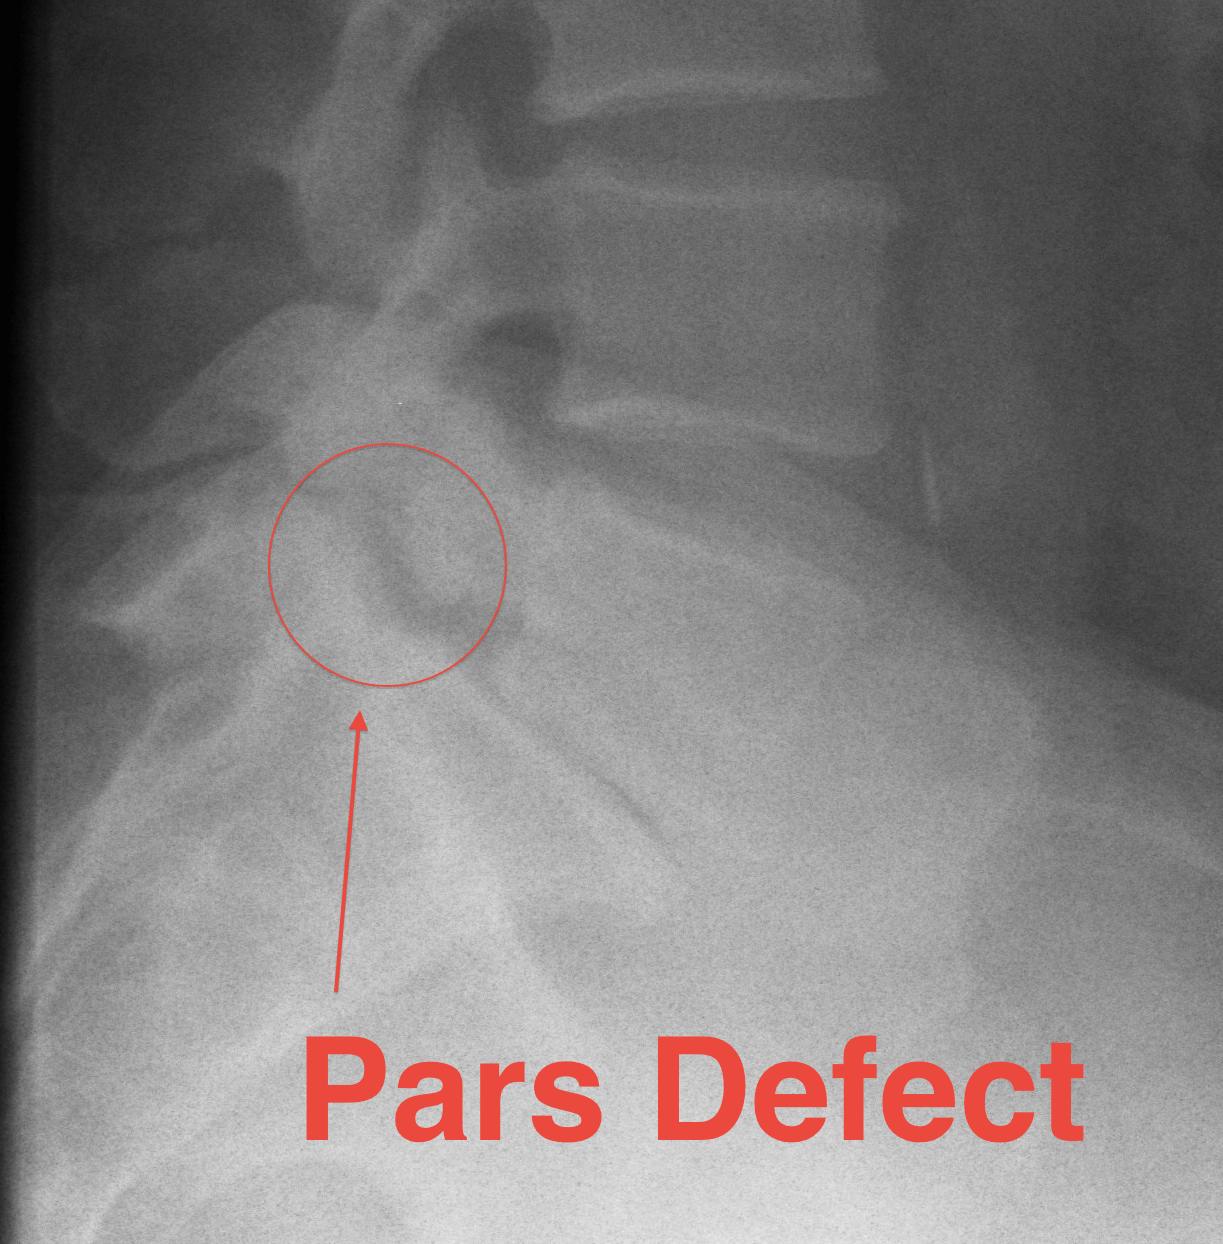

Spondylolysis

Definition

- radiolucent defect of pars

Types

- acute - narrow gap & irregular edges

- pars elongated & thinned

- chronic - wide gap with smooth sclerotic edges